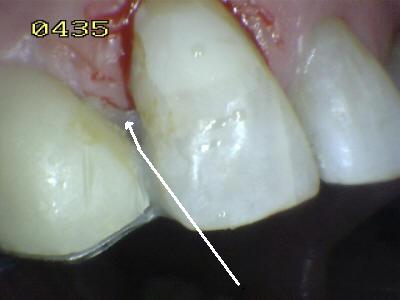

Cementado con la goma dique.  Observe los excesos de cemento de resina de curado dual (flechas blancas)